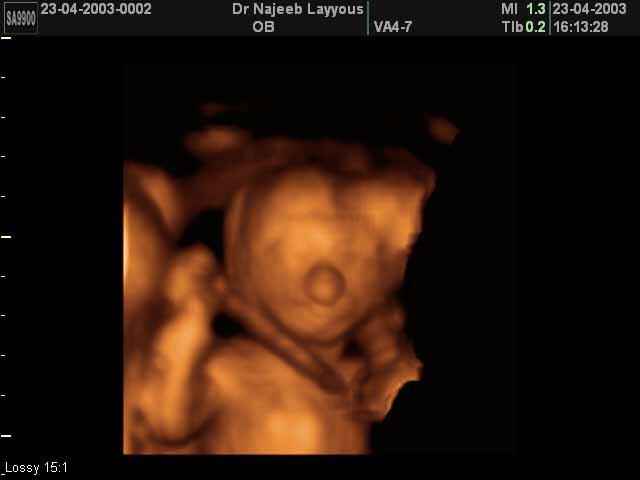

3D second trimestre échographie Photos de numérisation - deuxième partie de la grossesse